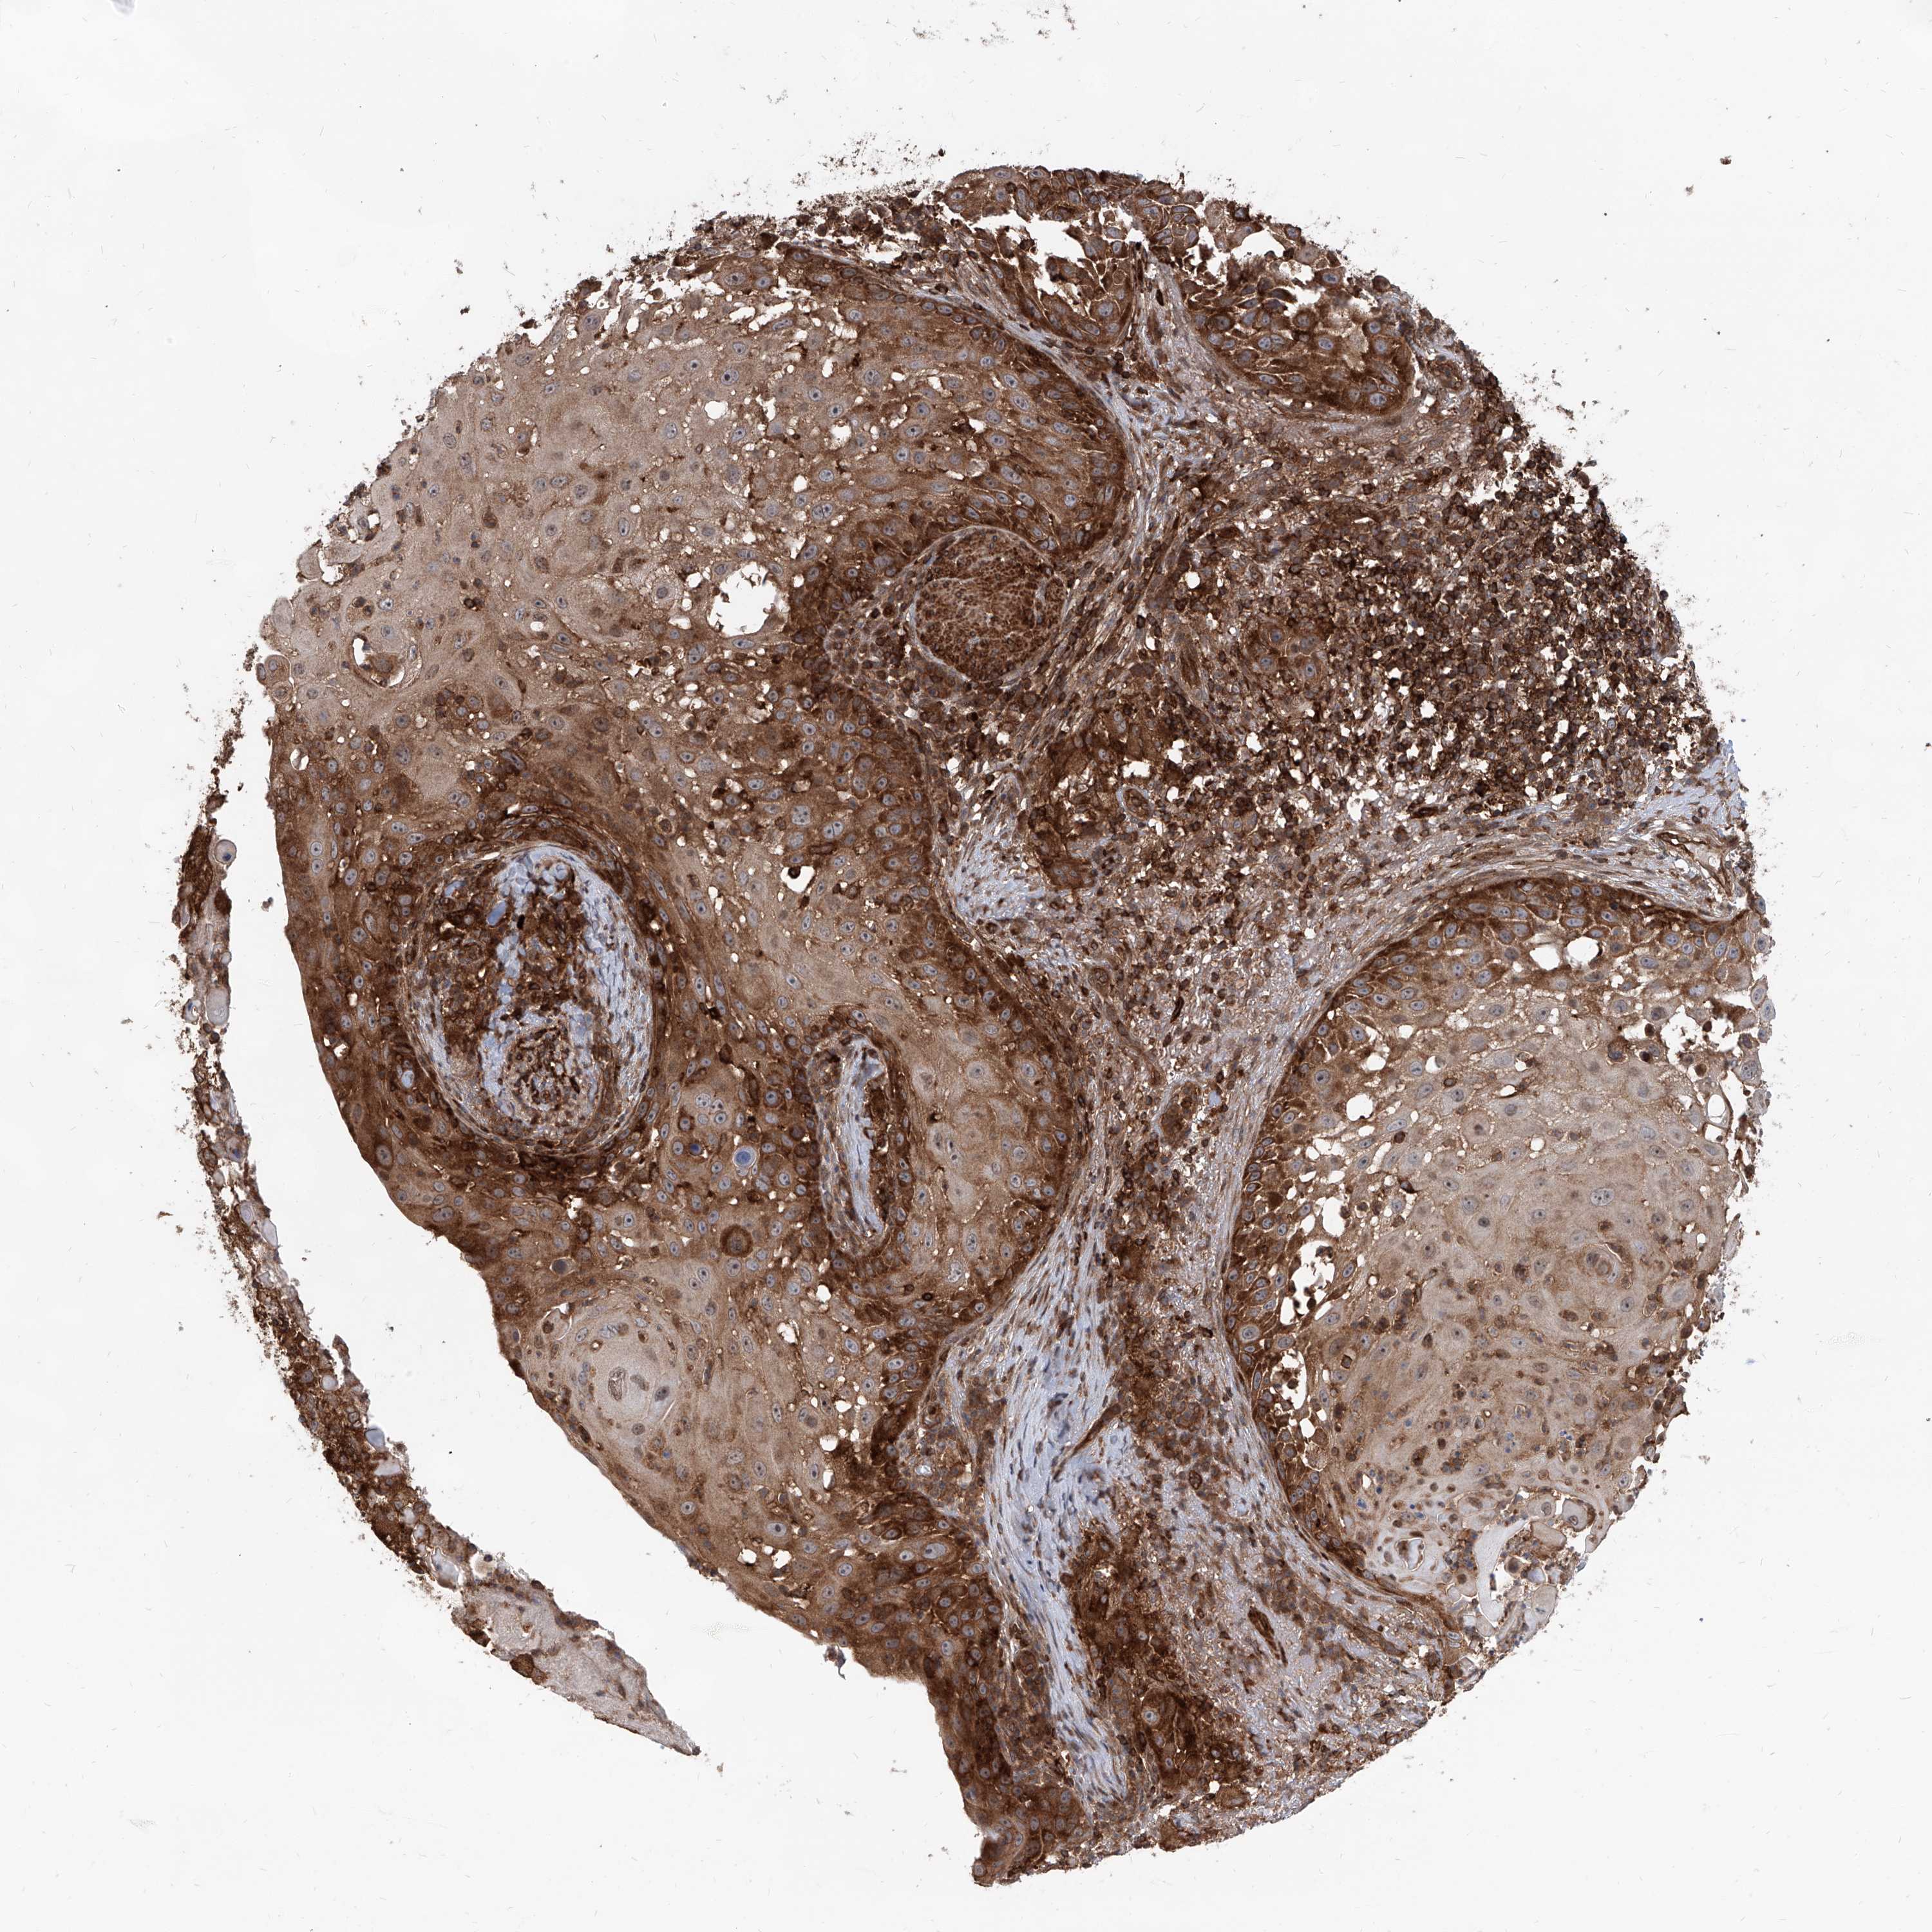

Basal cell and squamous cell cancer

SKIN CANCER - Protein expressioni

A mouse-over function shows sample information and annotation data. Click on an image to view it in a full screen mode. Samples can be filtered based on level of antibody staining by selecting one or several of the following categories: high, medium, low and not detected. The assay and annotation is described here.

Each image is clickable and will lead to virtual microscopy that enables deeper exploration of all samples and also displays staining intensity scores, fraction scores and subcellular localization as well as patient and tissue information for each sample.

Antibody HPA031572

Antibody HPA031573

Basal cell carcinoma

Squamous cell carcinoma, NOS

Squamous cell carcinoma, metastatic, NOS